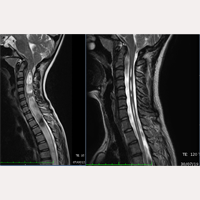

Between October 1993 and July 2017, more than 1000 patients affected by the Neuro-Cranio-Vertebral Syndrome and/or the Filum Disease with Arnold-Chiari I, Syringomyelia and Scoliosis (in different diagnostic combinations) have been treated according to the guidelines of the FILUM SYSTEM®.